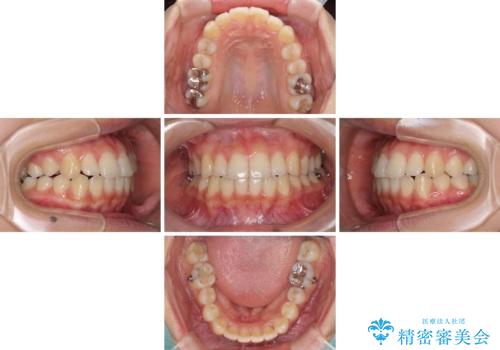

前歯の突出感とデコボコ インビザラインで改善

- 上下前歯のデコボコを気にして来院された患者様です。

インビザラインによる上下歯列の側方拡大と後方移動、IPR(歯と歯の間を削る)にるスペースの獲得により歯列を整えることとしました。

右上の小臼歯は歯根癒着をしており、様々な方法を試みるも動かすことができませんでした。

それでも奥歯のかみ合わせに不自由はなく、歯列をきれいに整えることができました。